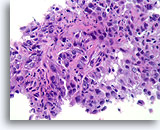

Ductaal carcinoom, Borst FNA, Celblok.

Kleine vergroting van de patiënt in afbeelding 65-66 toont de discohesieve monotone ductale celpopulatie met gerandomiseerde polariteit en een solide groeipatroon.

Ductaal carcinoom, Borst FNA, Celblok.

Kleine vergroting van de patiënt in afbeelding 65-66 toont de discohesieve monotone ductale celpopulatie met gerandomiseerde polariteit en een solide groeipatroon.